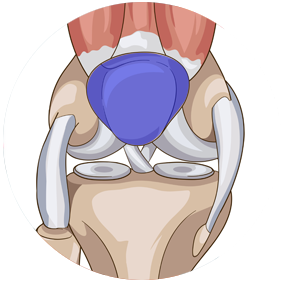

Chirurgie des ménisques

Les ménisques jouent un rôle d’amortisseurs entre le fémur et le tibia. Mal vascularisés, ils cicatrisent difficilement, aussi la présence d'une lésion nécessite parfois une intervention afin de guérir et stabiliser l'articulation.